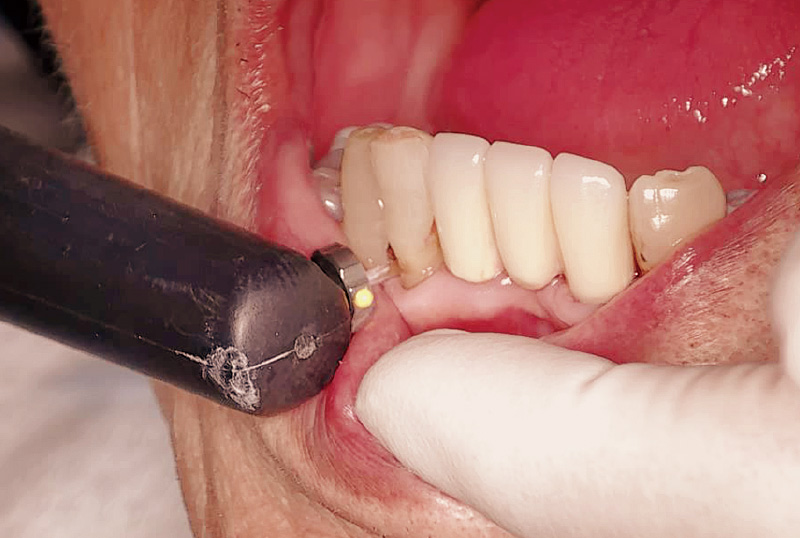

プロフェッショナルケア(図10)を終えると、最後に「ダイアグノデント ペン」を使って、う蝕の有無や初期う蝕の進行度合いをチェックします(図11)。当院では、初期う蝕を早期に発見し、適切なタイミングで介入できるよう、「ダイアグノデント ペン」の検査結果をチェックシートに記入し、管理しています。数値で客観的にお見せすることで、患者さんのモチベーションアップや継続管理に大いに役立っていると感じています(図12)。

図11 プロフェッショナルケア後に「ダイアグノデント ペン」を用いて、測定を行う。 -